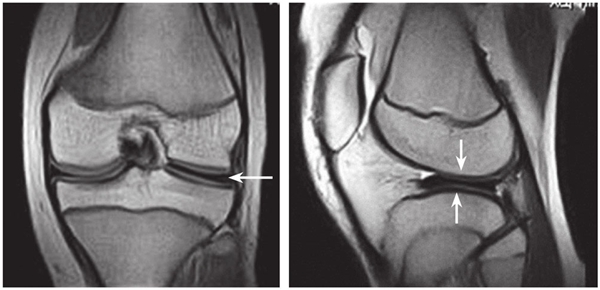

目前临床较常用的是MRI诊断,当看到半月板向中央延伸,其厚度并未改变,就要怀疑盘状软骨。软骨的中央超过12mm,而且厚度一直不变,也是一个征象(图4-10-1-3)。

图4-10-1-3 盘状半月板MRI表现,外侧半月板明显增厚,向中央延伸